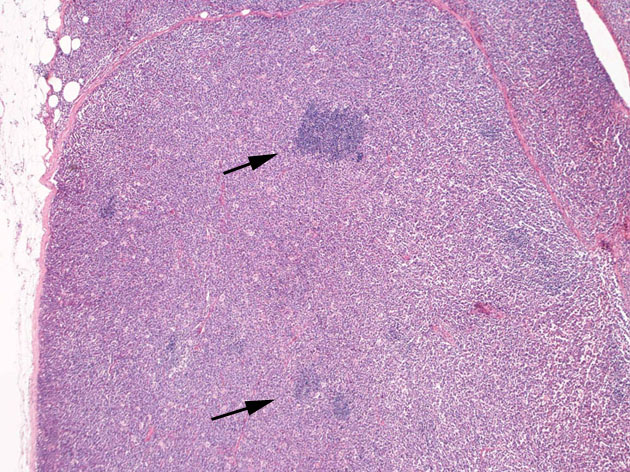

リンパ節病理組織所見

罹患リンパ節の基本構造は消失し腫瘍細胞のびまん性増殖で置換されている。非腫瘍性の小リンパ球(CD3+, CD4/8+)が濾胞様に散在して残る(Fig.01)。不整型または類円形の明るい核をもつmedium-sizeのリンパ球様細胞が密に増殖している。細胞質は乏しい(Fig.02)。CD68陽性macrophageが多く混在する部分が認められた。